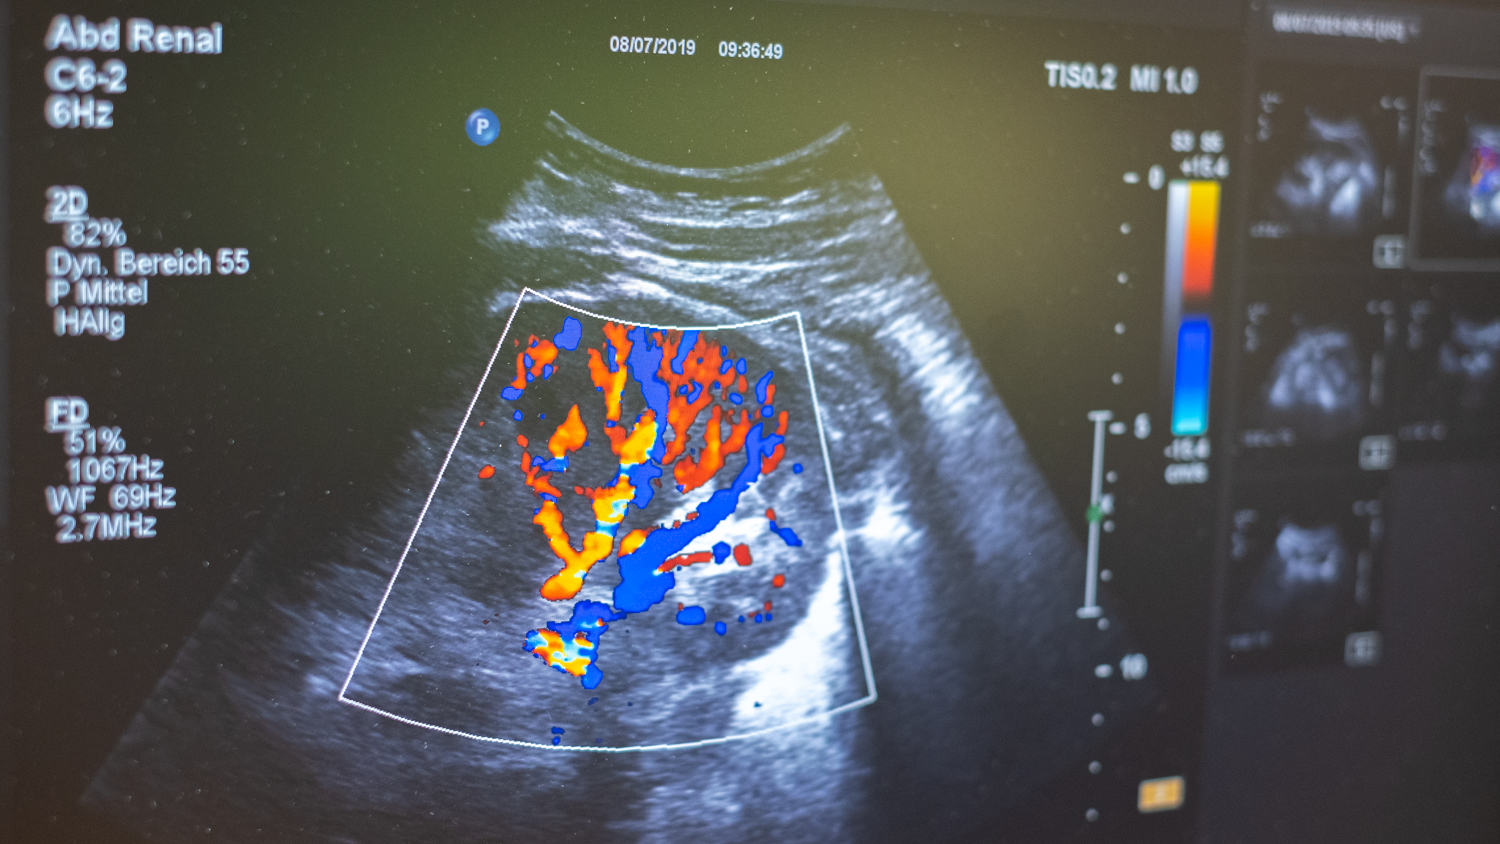

Sonographie der Nieren und Nierengefäße

Die Praxis verfügt über ein modernes, neues Ultraschallgerät, EKG, Ergometer, Abfragegeräte für Schrittmacher, Eventrecorder und Defibrillatoren sowie Notfallequipment.